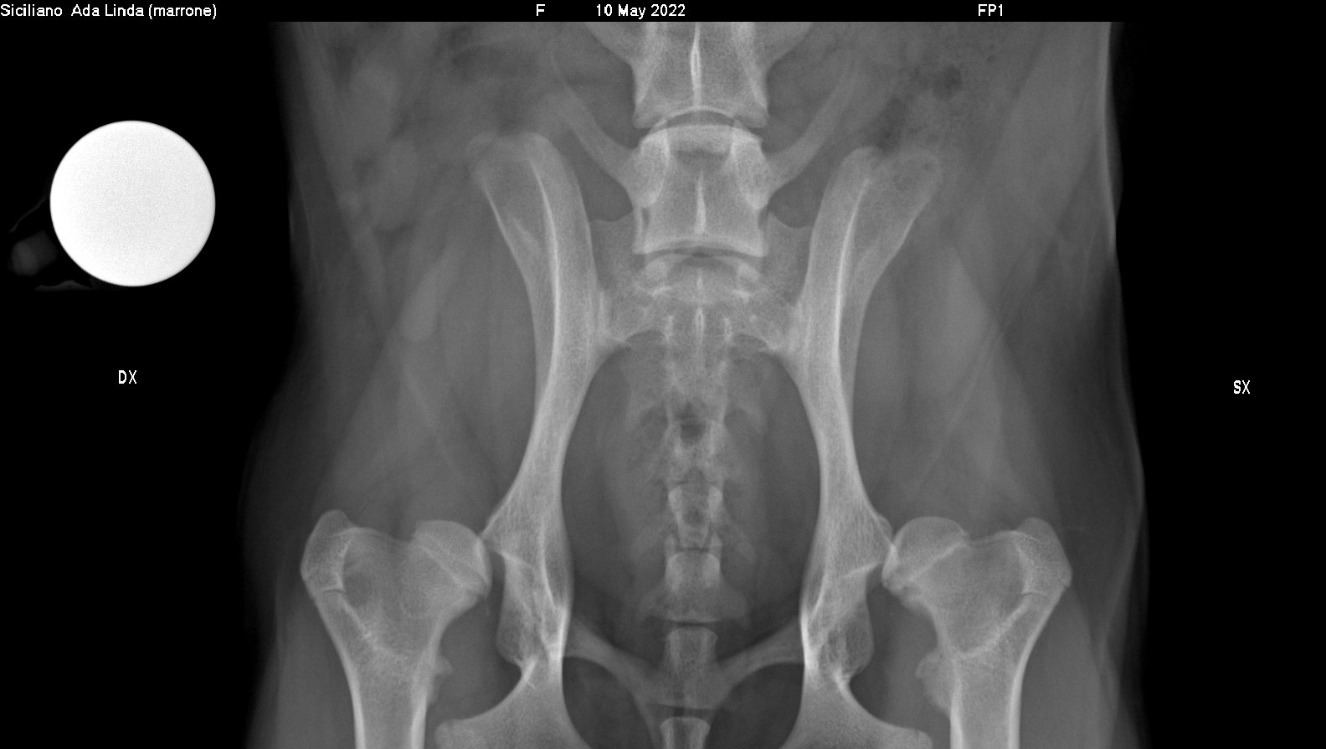

Luna e Linda sono due cucciole di cocker prese in carico dall'associazione Italian Cocker Rescue ODV nate con una gravissima malformazione delle anche, entrambe hanno una totale sublussazione, ovvero le teste dei femori completamente fuori dall'acetabolo.